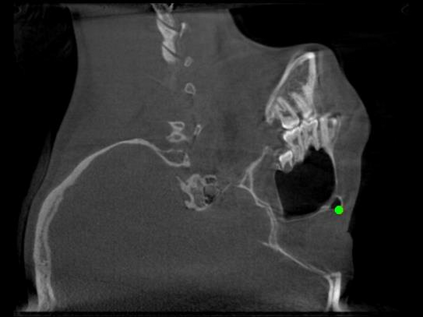

Detecting 3D landmarks on cone-beam computed tomography (CBCT) is crucial to assessing and quantifying the anatomical abnormalities in 3D cephalometric analysis. However, the current methods are time-consuming and suffer from large biases in landmark localization, leading to unreliable diagnosis results. In this work, we propose a novel Structure-Aware Long Short-Term Memory framework (SA-LSTM) for efficient and accurate 3D landmark detection. To reduce the computational burden, SA-LSTM is designed in two stages. It first locates the coarse landmarks via heatmap regression on a down-sampled CBCT volume and then progressively refines landmarks by attentive offset regression using multi-resolution cropped patches. To boost accuracy, SA-LSTM captures global-local dependence among the cropping patches via self-attention. Specifically, a novel graph attention module implicitly encodes the landmark's global structure to rationalize the predicted position. Moreover, a novel attention-gated module recursively filters irrelevant local features and maintains high-confident local predictions for aggregating the final result. Experiments conducted on an in-house dataset and a public dataset show that our method outperforms state-of-the-art methods, achieving 1.64 mm and 2.37 mm average errors, respectively. Furthermore, our method is very efficient, taking only 0.5 seconds for inferring the whole CBCT volume of resolution 768$\times$768$\times$576.